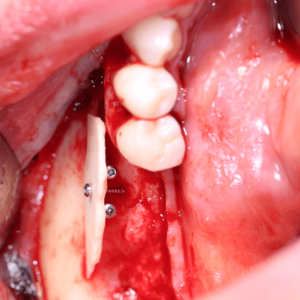

Eine Rekonstruktion des Alveolarkamms ist für die vorhersagbare Implantation oftmals unausweichlich. Deshalb ist es wichtig, das für den Patienten bestmögliche Augmentationsverfahren auszuwählen und dessen Möglichkeiten und Limitationen, abhängig von der Defektgeometrie, richtig einzuschätzen. Das Referententeam Dr. Dr. Diana Heimes und Univ.-Prof. Dr. Dr. Peer Kämmerer, MA, FEBOMFS, stellt Ihnen ein bewährtes und wissenschaftlich fundiertes

Konzept vor. Systematisch werden verschiedene Defektgeometrien mit den für sie passenden Augmentationstechniken verbunden. Die aktuellen wissenschaftlichen Daten und die Patientenbedürfnisse werden eingehend beleuchtet, um Ihnen neue Wege bei der Versorgung Ihrer Patienten zu ebnen.

Dabei werden verschiedene Knochenersatzmaterialien sowie deren Indikationen kritisch diskutiert und Ihnen die neuesten Erkenntnisse zur Verbesserung der Hart- und Weichgewebeheilung nähergebracht. Die spezifischen Eigenschaften der einzelnen Materialien und deren Anwendung in verschiedenen Indikationen werden detailliert betrachtet. Zusätzlich zur Theorie können Sie sich die Techniken durch die Hands-on-Übungen selbst aneignen.